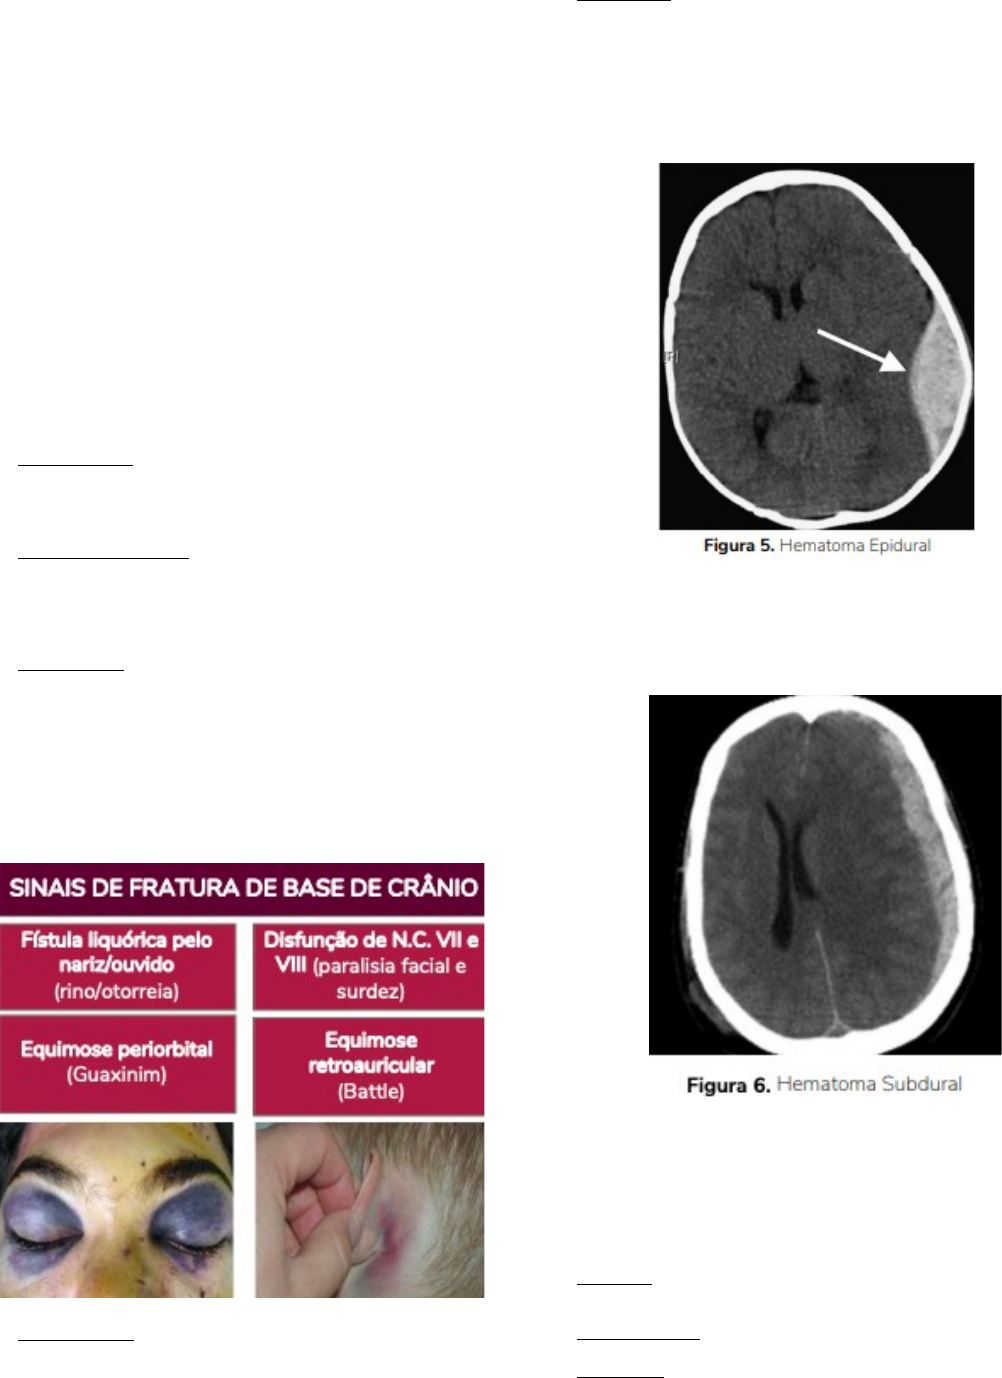

Lesão Focal=São os vários hematomas que podem ocorrer.

Hematoma Epidural:

É um tipo relativamente raro, estando presente em apenas 0,5% dos pacientes com TCE. A causa mais comum de sua origem é um sangramento arterial por lesão da Artéria Meníngea Média.

O sangramento empurra a dura para o lado oposto da estrutura óssea do crânio dando aspecto de biconvexo na TC.

Hematoma Subdural:

Presente em cerca de 30% dos pacientes com TCE grave. A principal causa é a ruptura de pequenos vasos superficiais ou vasos ponte do córtex cerebral, de modo que não mais ocorre o deslocamento da dura e aí o sangue se acumula no espaço subaracnoide. O aspecto na TC é de côncavo-convexo.